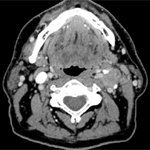

Researchers found that there is an increasing incidence of late stage head and neck cancer in the U.S., highlighting the need for continuous public health efforts toward early detection.

A new possible surveillance model suggests scanning patients with head and neck cancer treated with radiotherapy less frequently could be more cost-effective and time-effective.

A new study looked at what methods were used to detect recurrences of human papillomavirus (HPV)-associated oropharyngeal squamous cell carcinoma to see if surveillance guidelines recommended by the National Comprehensive Cancer Center were effective.